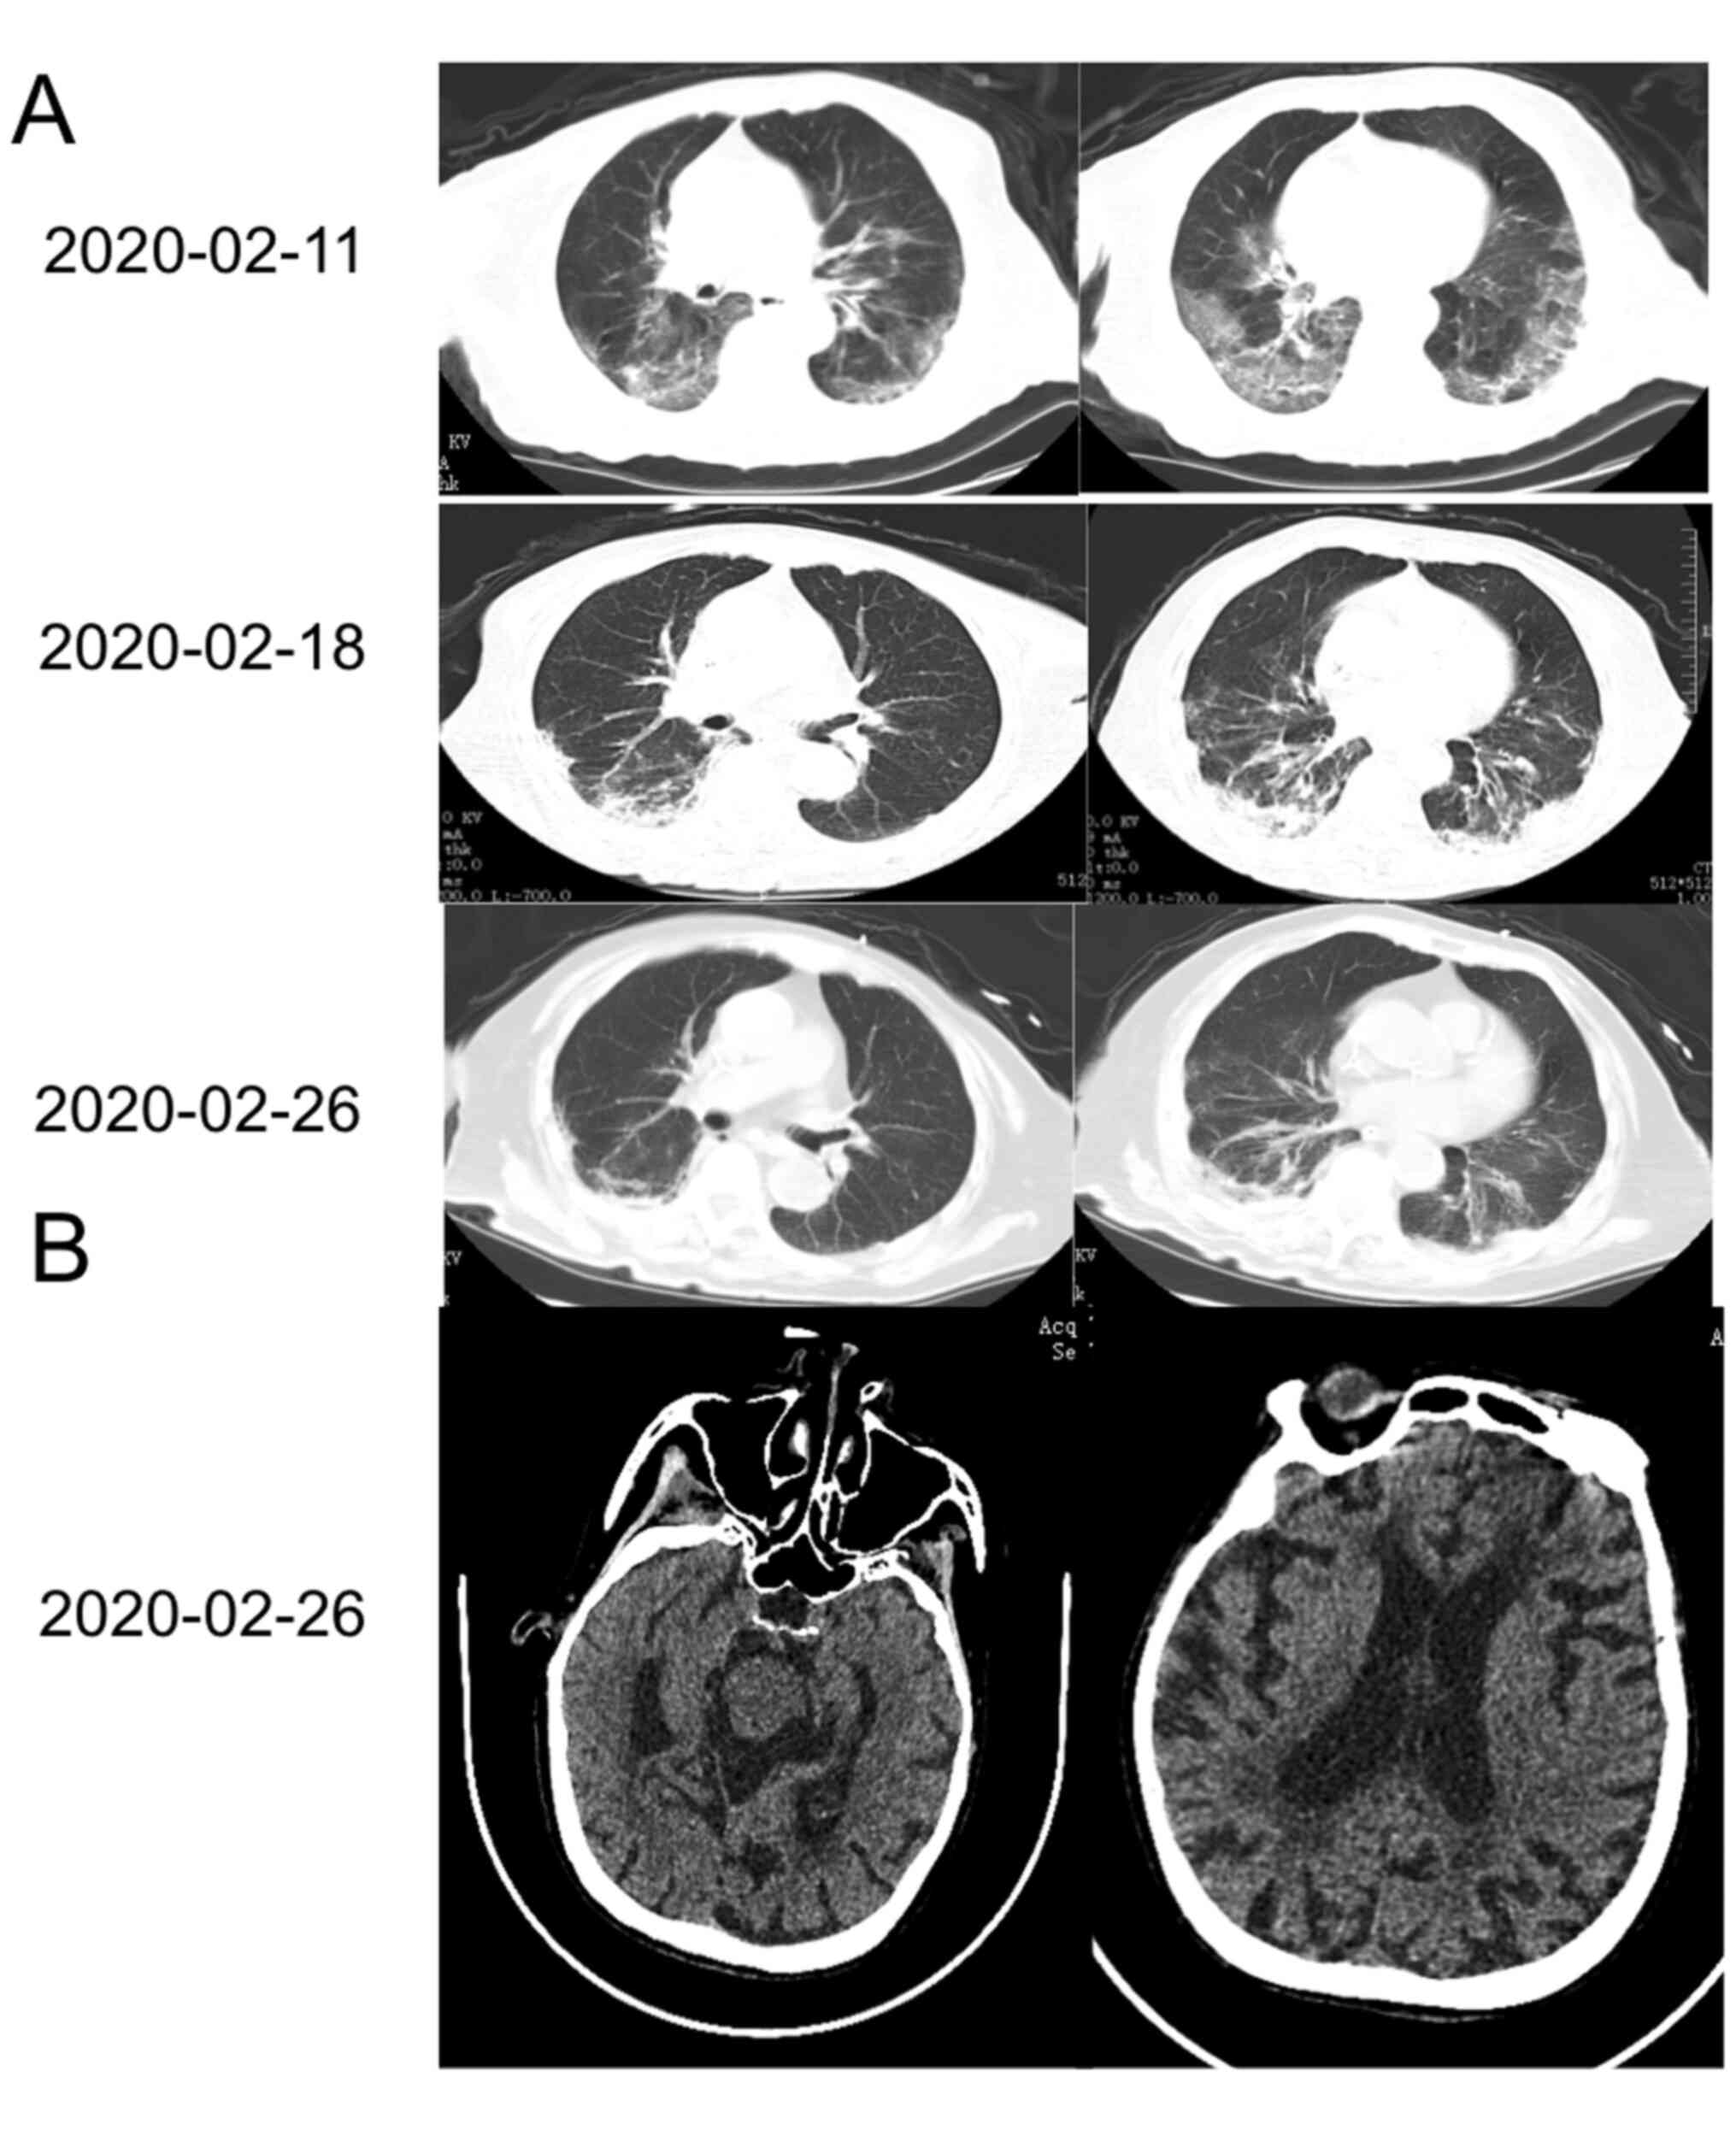

The patient exhibited gradual improvement with absorption of the ground glass opacity on chest CT (Fig. 1A). 25 days after disease onset, the patient suddenly became unconscious and the Glasgow Coma Scale score was determined to be 6. On neurological examination, the patient was irresponsive to voice and painful stimulation, her pupils were isochoric (2-mm diameter) and reactive, and there was no autonomous activity in any limbs. There were significantly increased muscle tension, positive cortico-spinal tract signs on both sides, a positive meningeal irritation sign, obvious neck stiffness, and a positive Kernig sign. Brain CT was unremarkable compared with a previous brain MRI (Fig. 1B); however, the patient was not subjected to brain MRI at this time-point.

Figure 1

Representative CT and MRI images of the patient. (A) Chest CT images revealed bilateral GGO and segmental areas of consolidation at 11 days after disease onset. These GGOs were gradually resolved by days 18 and 26 after disease. (B) The head CT on the day that the patient entered the coma, which did not present any remarkable findings. GGO, ground-glass opacity.